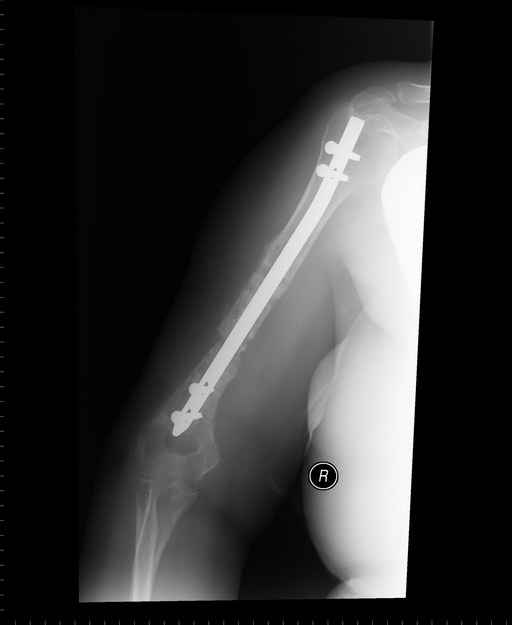

Больная 48 лет, медсестра-массажист, перелом плеча 7 лет назад, оперирована 4-кратно и безуспешно

Больная 48 лет, медсестра. Травма получена 7 лет назад, оперирована первично в Турции - остеосинтез пластиной - несращение - реостеосинтез стержнем там же через год (обычным, с выстоянеием его в полость плеча) - несращение - поступила к нам впервые в марте 2008 года - удаление стержня, реостеосинтез пластиной и костная пластика, в течение 2 лет лизис кости вокруг винтов, смещение фиксатора, в марте 2010 - удаление пластины, реостеосинтез интрамедуллярным стержнем с блокированием (рассверливание + костная пластика). В динамике - вновь лизис в области перелома, нестабильность дистальных блокирующих винтов.

Да, принципиально что-то такое тут подошло бы. Но тут дефект, и надо точно подсчитать, не длинноват ли стержень, а то, может, после плотного контакта он вылезет в локтевую ямку.

Клинически фиксация пока действительно стабильна, но на рентгенограммах резорбция кости в области дистальных блокирующих винтов и миграция одного из них.